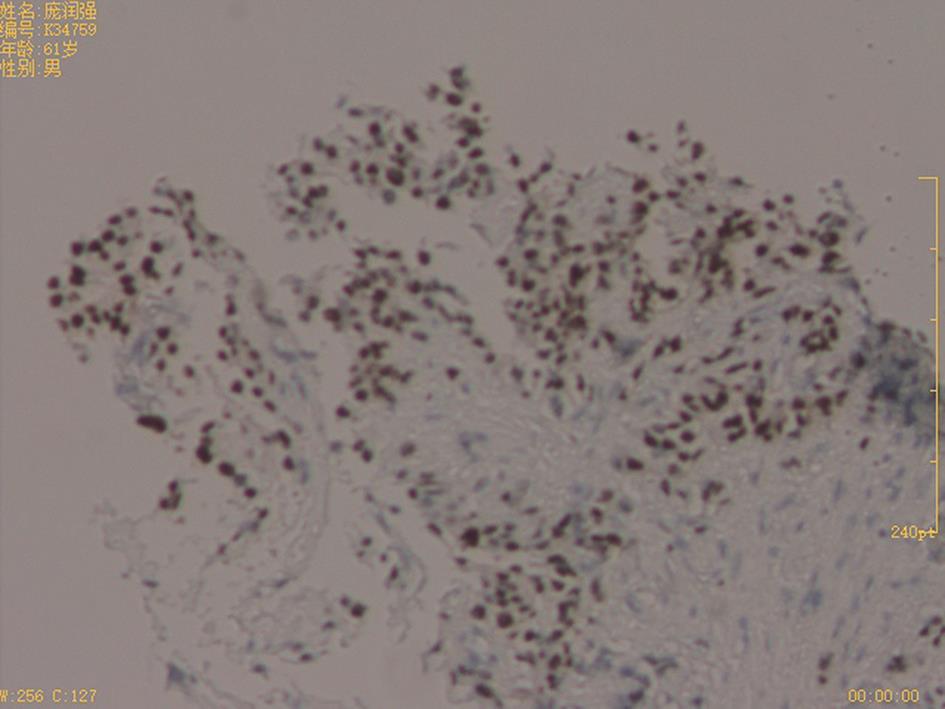

摘要:目的 探究肿瘤相关成纤维细胞作为生物学标志物预测非肌层浸润性膀胱癌(non-muscle invasive bladder cancer,NMIBC)患者术后复发的临床意义。方法 从基因表达综合(Gene Expression Omnibus,GEO)数据库下载转录组数据以及对应的临床信息,分析原发性和复发性膀胱癌样本中ACTA2的表达差异。免疫组织化学法(immunohistochemistry,IHC)检测56例膀胱癌样本中α-平滑肌肌动蛋白(α-smooth muscle actin,α-SMA)表达。绘制无复发生存曲线(recurrence-free survival,RFS)和时间依赖性受试者工作特征曲线(time-dependent receiver operating characteristic curves,tdROC)。采用单变量和多变量Cox比例风险回归模型分析α-SMA作为膀胱癌患者术后复发的预测因素的可行性。结果 GSE13507、GSE120739和GSE128959数据集复发组中ACTA2的表达均高于原发组(P<0.05)。IHC结果显示,α-SMA蛋白定位在肿瘤间质,复发组中α-SMA阳性/强阳性占比56.52%,而在原发组中占比16.13%,差异有统计学意义(P<0.001)。α-SMA蛋白表达与年龄、性别、病理分期、分级、肿瘤数量和大小等指标无明显相关性。α-SMA高表达组患者术后RFS较低表达组患者明显缩短[风险比(hazard ratio,HR)=2.76,95%可信区间(confidence interval,CI)=1.21~6.30,P=0.016]。多变量Cox分析显示,α-SMA蛋白表达水平是影响患者术后RFS的独立危险因素(HR=2.47,95%CI=1.02~5.97,P=0.045)。tdROC曲线提示α-SMA对复发的预测能力优于其他临床因素。结论 肿瘤间质的α-SMA蛋白表达水平与膀胱癌复发密切相关,可作为临床预测NMIBC患者术后复发的标志物。